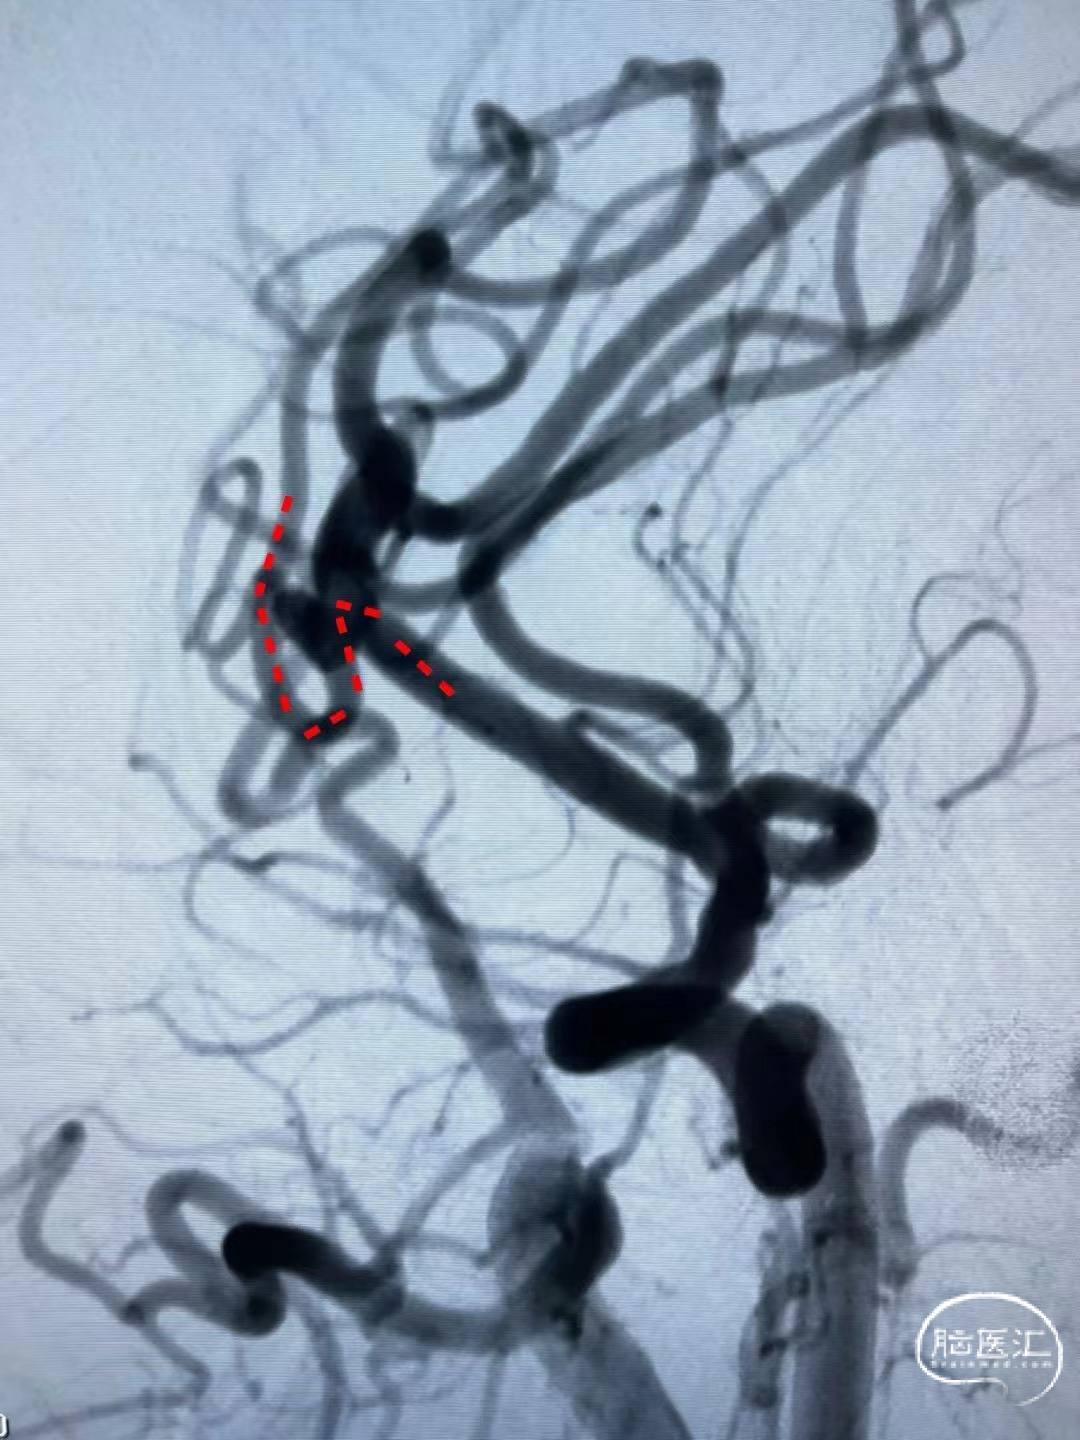

造影提示:动脉瘤瘤颈累及上下干支,下干支与M1成角较锐S弯;患者右侧颈内动脉非常迂曲。

3D造影成像:动脉瘤大小约3.7*3.1mm。

手术过程

Synchro14微导丝牵引支架微导管到位;弹簧圈微导管到位。

送入3*6mm弹簧圈成篮,同时摆一根支架微导管在上干,为T型支架做准备;

释放一枚Leo baby支架 2.5*25mm。

因下干支与M1成角太锐,支架在转弯处打开,多次推拉调整,以“神龙摆尾”方式释放,将支架尾端避开上干开口。

释放支架后,再依次送入2*3mm、1.5*2mm两枚弹簧圈完成治疗。

术后造影显示各分支血管通畅,动脉瘤不再显影。